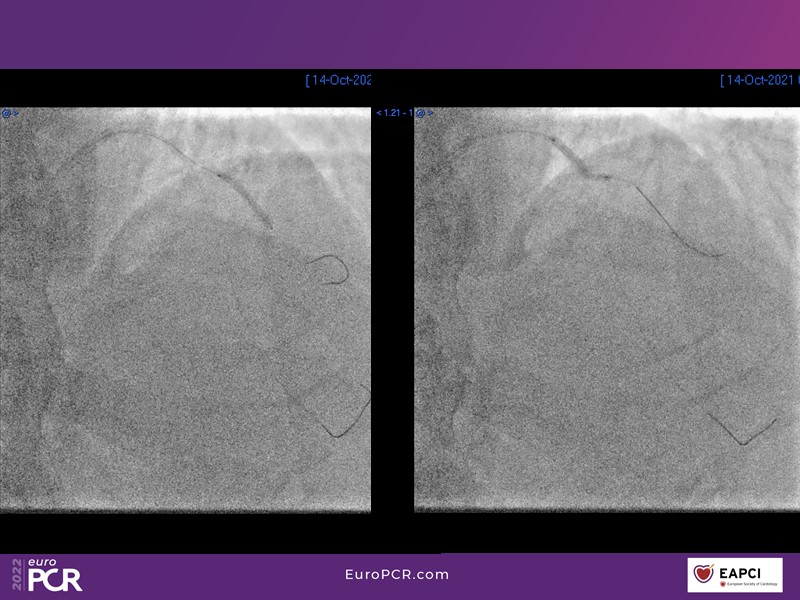

Alexandre Abizaid, Marco Valgimigli, Fazila Malik, Luca Testa, Patrick W. Serruys, Damiano Regazzoli, Kumar Prathap, and Sandeep Basavarajaiah take turns in this session to discuss two innovative technologies: a stent platform with nanotechnology and a novel drug-coated balloon (DCB). These novel technologies both have unique features that could change daily practice and improve outcomes.

- To find out more about the application and mechanism of a sirolimus coated balloon for coronary artery disease treatment with case presentations in complex settings

- To look at the technology behind the products, what the key data suggest and important takeaways from case permutations